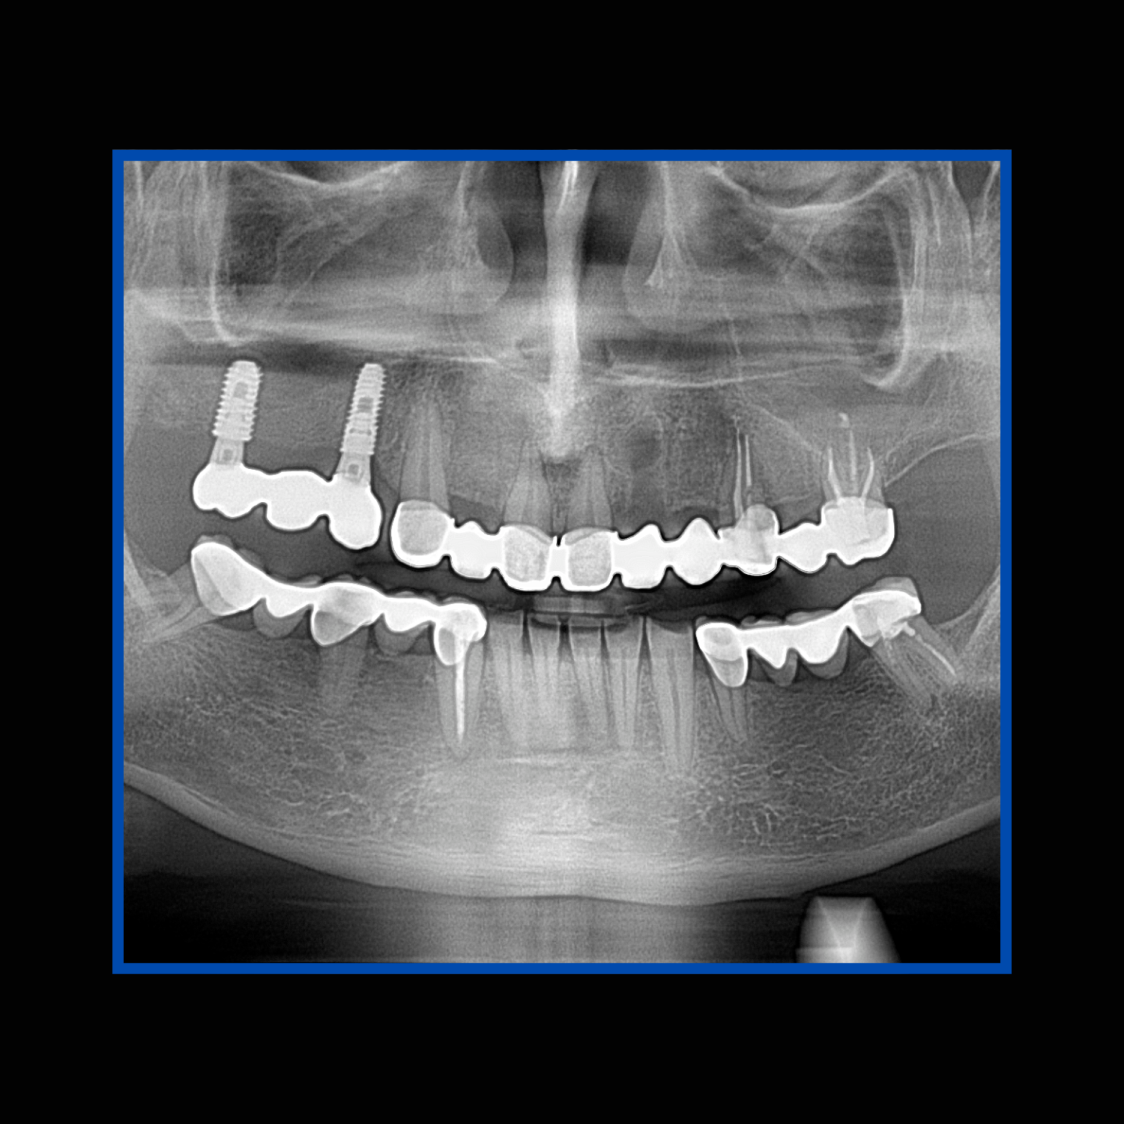

İmplant etrafındaki kemik açıklığını kemik grefti ile tedavi ettiğimiz vakamız.